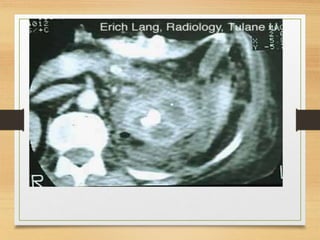

Radiological

• U/S

• C.T

CASE 4

• A 64-year-old man presents with a 2-month history

of painless visible haematuria, hypertension, weight

loss, loin swelling and anaemia. What is the most

likely diagnosis?